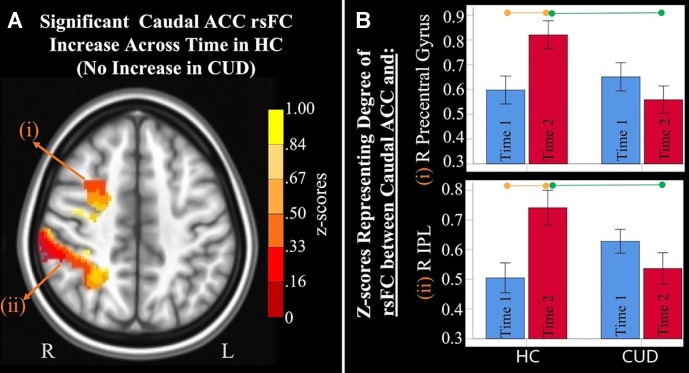

Interaction Effects: Differences in rsFC Changes Between Groups

Mixed-effects ANCOVA (controlling for alcohol use) revealed a significant group × time interaction in rsFC between caudal ACC and a) the right precentral gyrus and b) right inferior parietal lobule (f2). Post hoc analyses revealed that only the HC group (not the CUD group) showed a significant increase in rsFC between these regions across time. There were no other ACC or NAcc regions that showed group × time interaction effects. These effects remained significant when alcohol use, nicotine use, and IQ were covaried.

Additionally, ANCOVA results (“Methods,” section Data Denoising) showed that after controlling for the effects of the sum of the percent of variance accounted for by noise, differences in all clusters, shown in f2, were still significant (see F– and P-values in T4).

Table 4: Significant group× time interaction. Montreal Neurological Institute (MNI) coordinates of clusters (center of mass) in which resting functional connectivity (rsFC) of caudal anterior cingulate cortex (ACC) showed a significant (per-voxel p = .001, cluster p = 0.025, two-tailed p = 0.0 5) Group (non-treatment-seeking individuals with cannabis use disorder vs. healthy controls) by time (Time 1 vs. 2) interaction (f1). No other significant interactions were found for other regions of interest. F and significance (Sig) p-values show analyses of covariance (ANCOVA) results controlling for the effects of differences in the sum of percent of variance accounted for by noise.

| RsFC between Caudal ACC and: | Hemisphere | Brodmann area | x, y, z | F | Sig (p-value) | Cluster Size (# voxels) |

|---|---|---|---|---|---|---|

| Precentral gyrus | Right | 6 | 30, −3, 50 | 14.09 | .001 | 471 |

| Inferior parietal lobule and precuneus | Right | 7 | 40, −42, 48 | 12.46 | .001 | 1,900 |

Differences in rsFC Changes Between Groups

Because participants were recruited from a college community within narrow age ranges (∼18–19 years old), all should have experienced similar rsFC changes characteristic of the adolescent-to-early adulthood transition. The lack of a normative increase in caudal ACC rsFC across time in the CUD group (vs. controls) suggests the possibility of long-term effects of cannabis use on brain functional organization. We previously reported similar findings in a different sample of adolescents where a different sample of HCs showed a significant increase in rsFC between caudal ACC and frontal regions across time, while adolescents with CUD did not (ref. 19). Current findings indicate that these seemingly detrimental effects extend into early adulthood in an independent sample with CUD who have not sought treatment. This significant interaction was found when examining rsFC of the caudal ACC. There is evidence that this region, known to mediate control of basic functions such as motor control and attention to action such as stimulus–response selection and inhibitory control (ref. 48, ref. 49), develops earlier than other ACC regions and continues to develop into early adulthood (ref. 17, ref. 50). Those with CUD failed to show the typical increases in intrinsic connectivity of a network needed for motor control seeded in caudal ACC found in HC (ref. 17, ref. 19). The implications of this finding need to be further explored with larger samples with more follow-up time points and within the context of behavioral/motor performance.